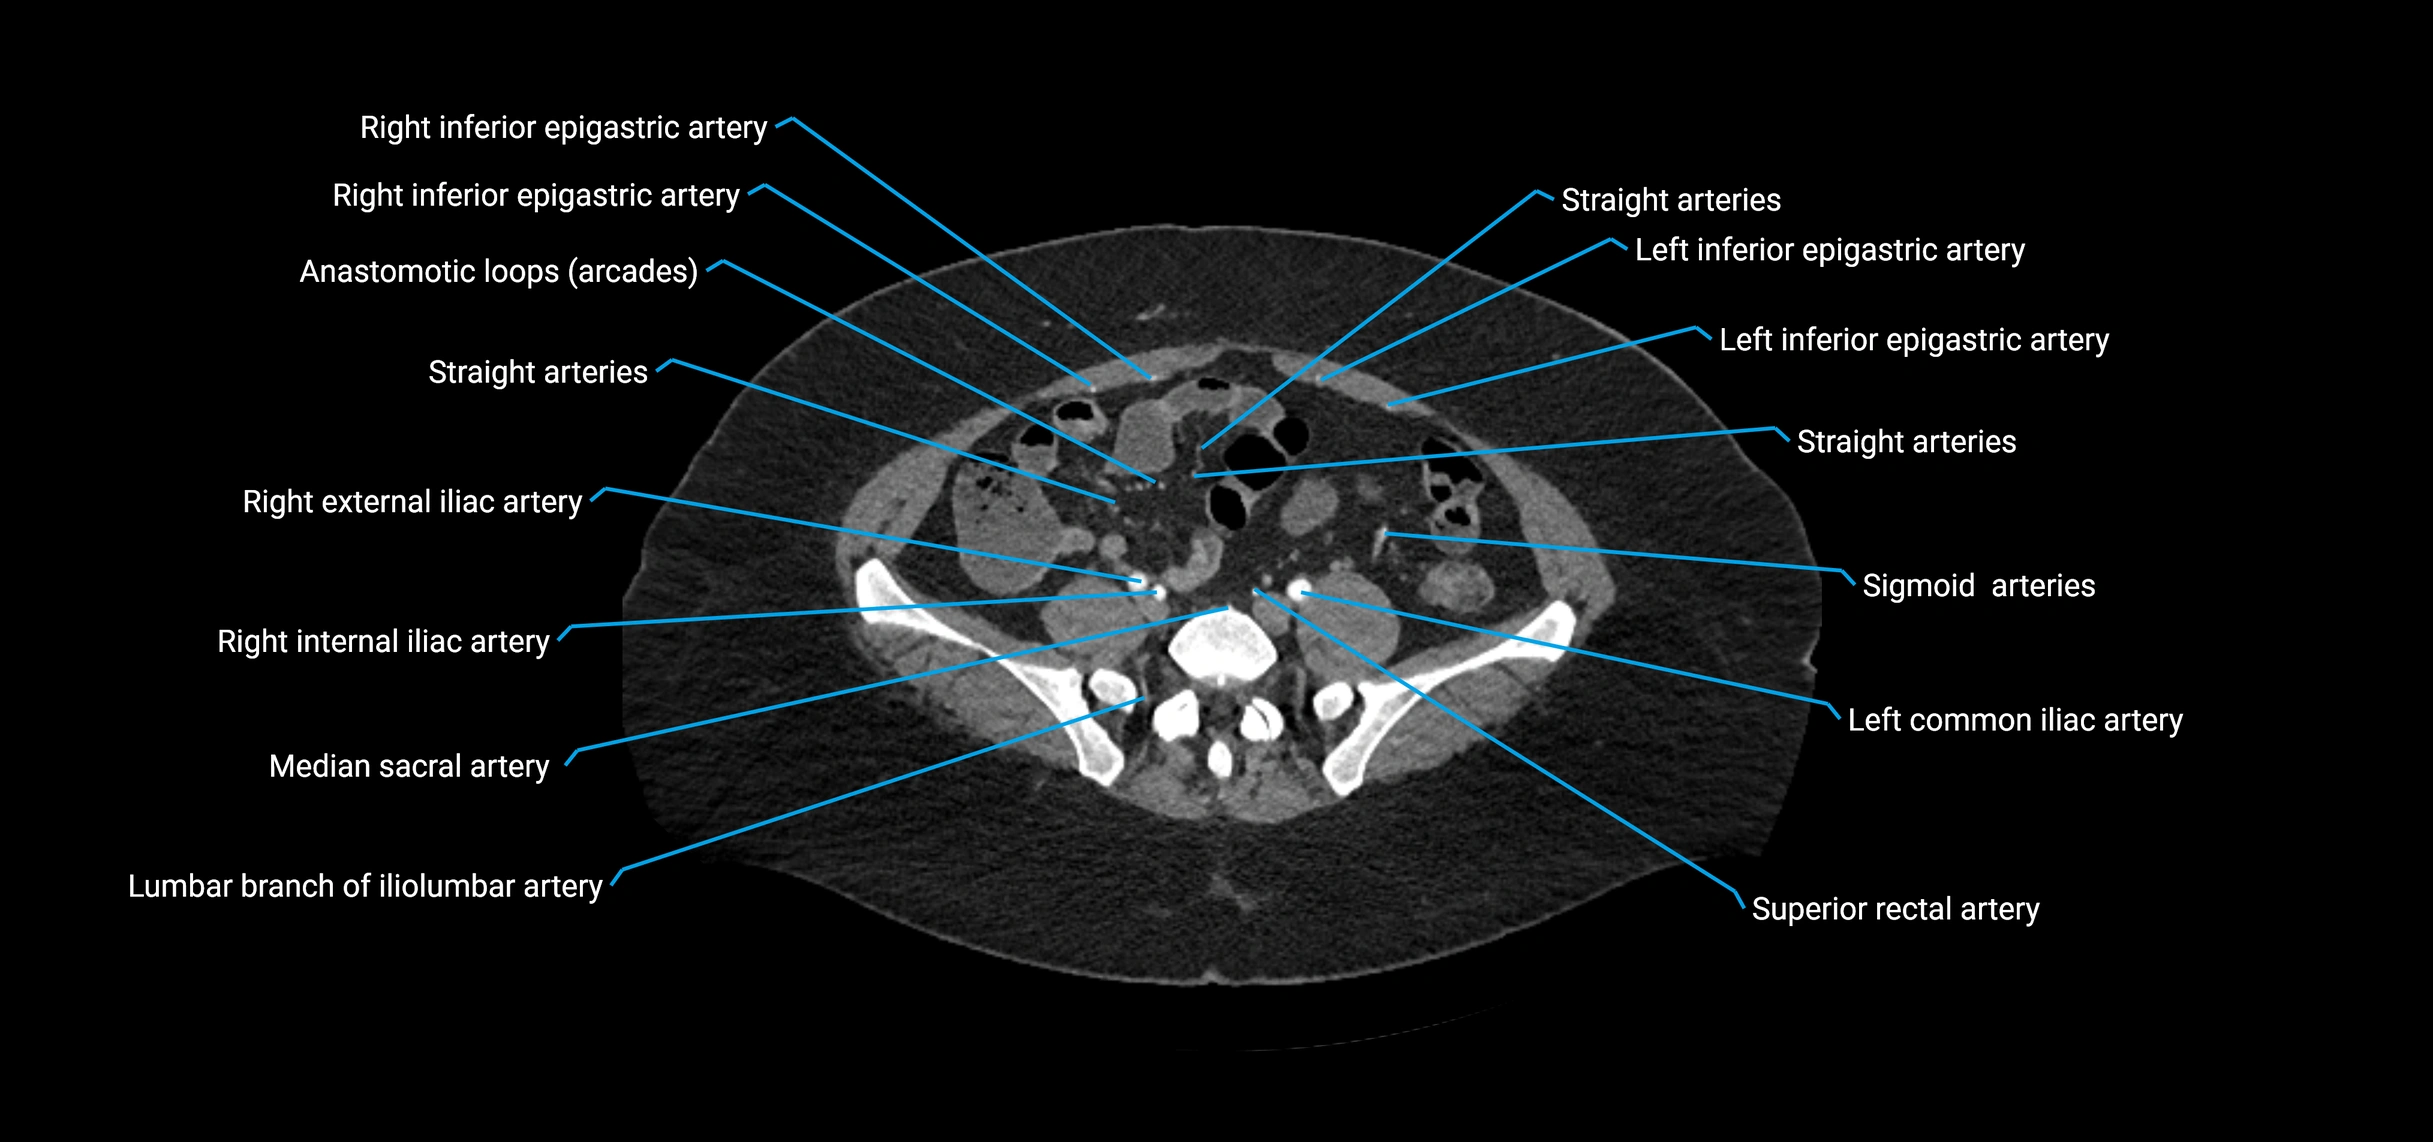

Contrast-enhanced CT (CTA):

• Gold standard for abdominal aortic imaging

• Provides excellent detail of lumen, wall, aneurysm, thrombus, and branch vessels

• Multiplanar and 3D reconstructions help in aneurysm measurement, stent graft planning, and dissection evaluation

• Detects acute rupture, traumatic injury, or occlusion with high sensitivity